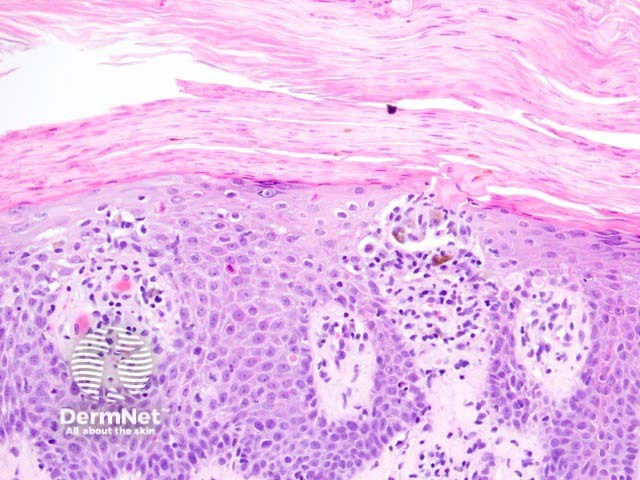

Histologically, keratosis lichenoides chronica is characterised by a lichenoid reaction pattern with marked basal cell death and vacuolar degeneration (figures 1-3). The dermal infiltrate shows a mixture of cells which may include plasma cells. The epidermal changes are highly variable — acanthosis, parakeratosis, and atrophy are all described features. Cornoid lamellae and eccrine infiltrates have been described.

Keratosis lichenoides chronica figure 1

Keratosis lichenoides chronica figure 2

Keratosis lichenoides chronica figure 3